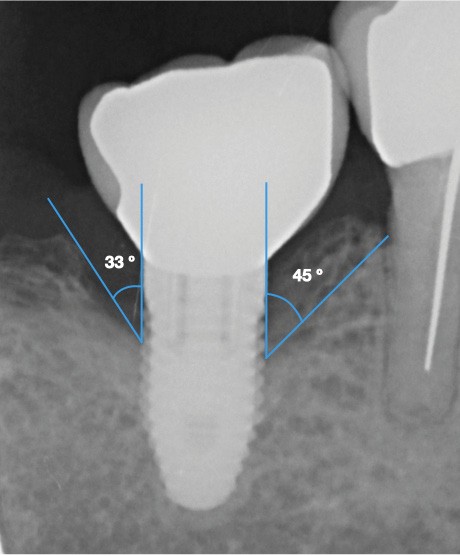

- Péri-implantite sur l’implant 47, diagnostiquée en août 2022

- Poches de 6 à 7 mm

- Implant posé en 2017

- Nobel Replace Select RP (4,1 x 10 mm)